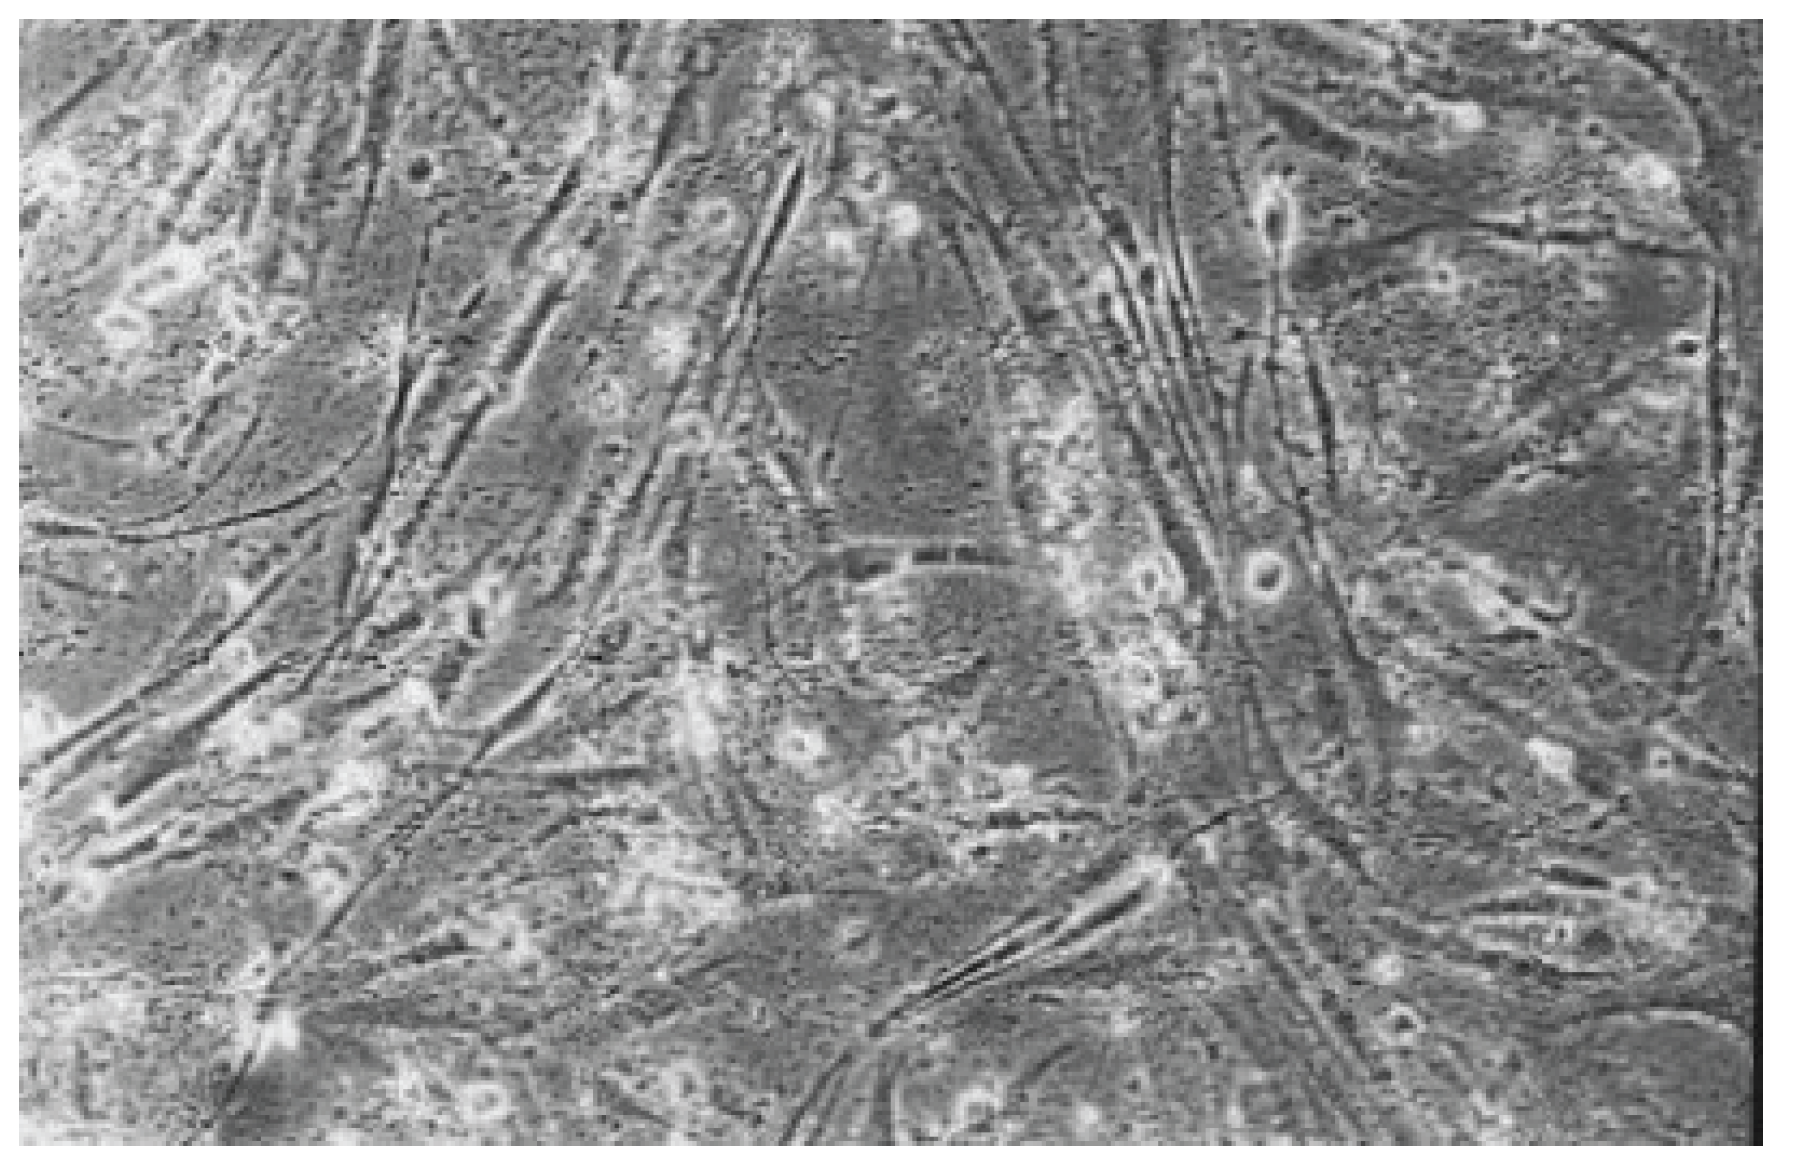

The qualitative evaluation is shown in Table 2, Table 3, Table 4, Table 5, Table 6 and Table 7. Figure 6, Figure 7, Figure 8, Figure 9, Figure 10, Figure 11 and Figure 12 depict the characteristic appearance of the cell cultures in the influence of the different dentin adhesive materials. The morphological phenotype of this cell line is characterised by spindle-shaped, long cells derived from the gingiva (HGPFC—human gingival primary fibroblast cells) representing human primary fibroblasts (pMF).

Figure 9. With AdheSE (No. 3), the cell culture appears less dense than the cell control. Some vital cells are recognizable (100-fold magnification).